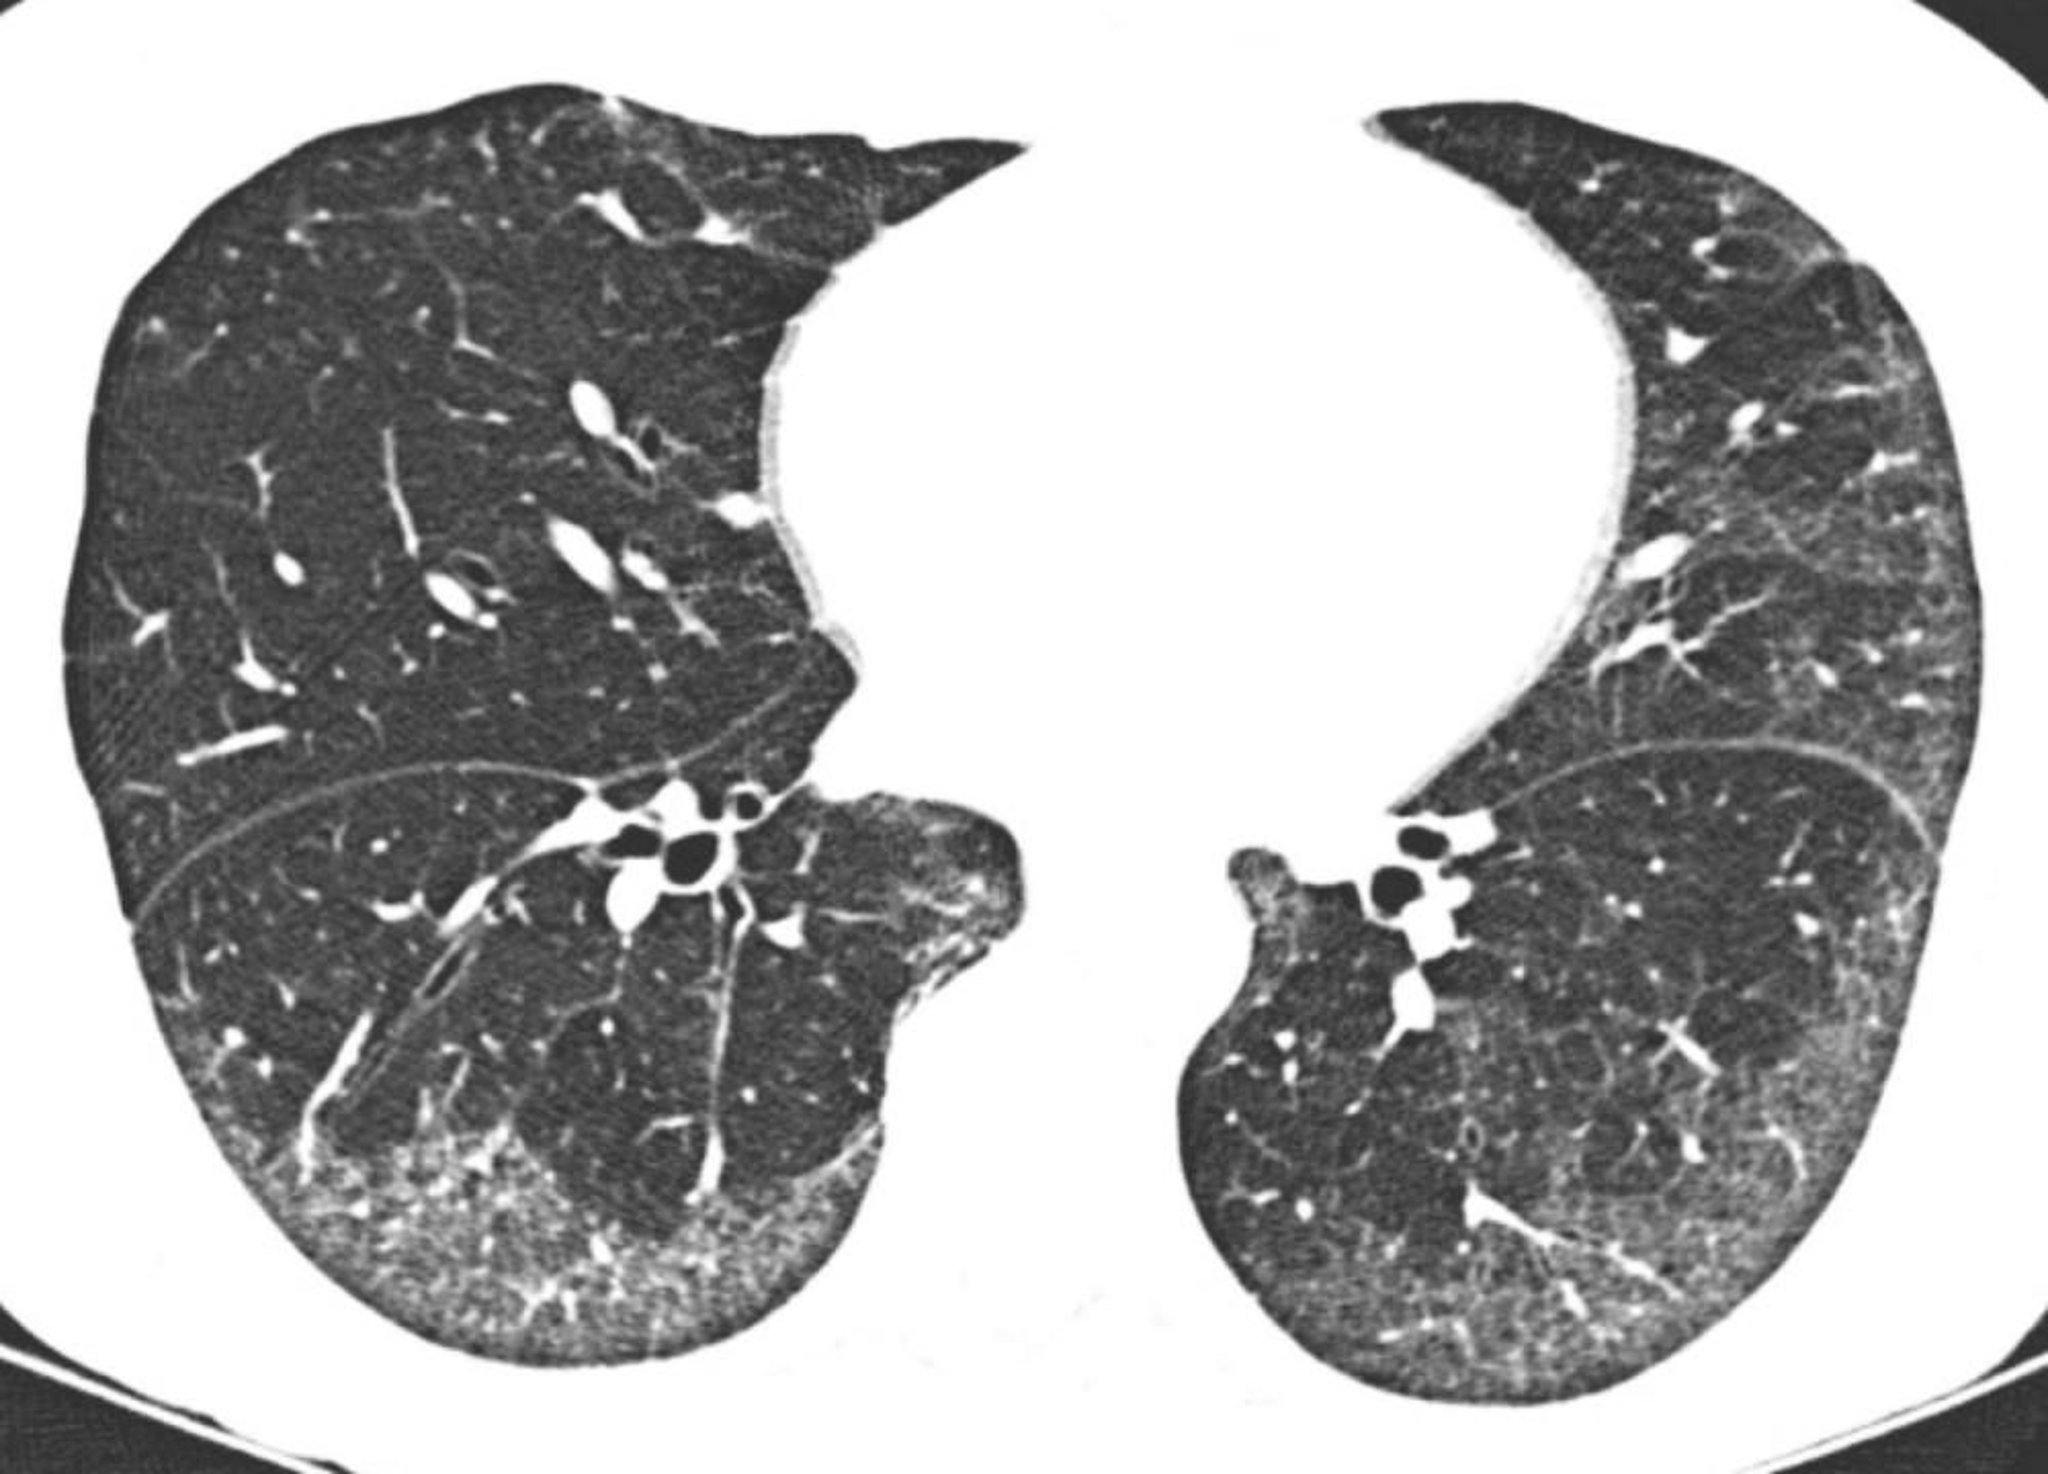

Polmonite interstiziale aspecifica idiopatica

La TC ad alta risoluzione mostra opacità prevalentemente a vetro smerigliato subpleuriche e basali. Il relativo risparmio del polmone direttamente al di sotto delle superfici pleuriche è tipico della polmonite interstiziale non specifica.

Image courtesy of Harold R. Collard, MD.